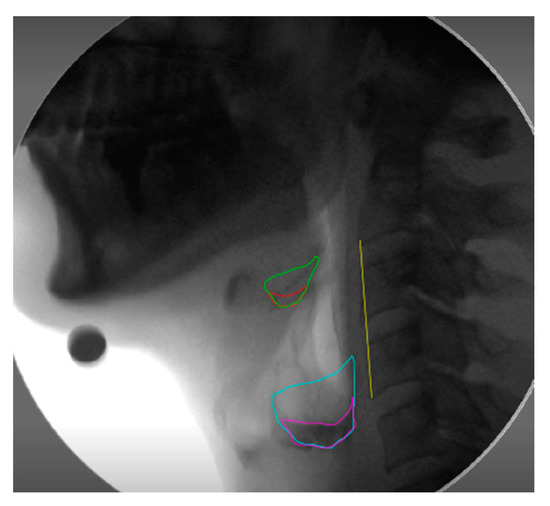

2.4.3. Laryngeal Excursion

2.4.6. Residue Severity Ratings (RSV)

2.4.7. NRRS Residue Measures